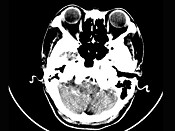

[单选题]女,45岁,右耳听力下降半年余,CT检查如图,最可能诊断为()A.继发性胆脂瘤B.脑膜瘤C.三叉神经瘤D.原发性胆脂瘤E.听神经瘤

[单选题]女,45岁,右耳听力下降半年余,CT检查如图,最可能的诊断是()A.继发性胆脂瘤B.脑膜瘤C.三叉神经瘤D.原发性胆脂瘤E.听神经瘤

[单选题]女,45岁,右耳听力下降半年余,CT检查如图,最可能的诊断是A.继发性胆脂瘤B.脑膜瘤C.三叉神经瘤D.原发性胆脂瘤E.听神经瘤

[单选题]女,45岁,右耳听力下降半年余,CT检查如图,最可能的诊断是( )。A.继发性胆脂瘤B.脑膜瘤C.三叉神经瘤D.原发性胆脂瘤E.听神经瘤